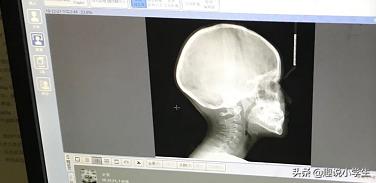

一週間後、その歯科病院の矯正歯科医に再登録したところ、一瞥して非常に深刻だと言い、すぐにフィルム撮影の手配をしてくれた。医師は、この子の永久切歯が切歯の萌出を制限しており、上顎骨の発育をすぐに刺激しなければならない、つまりすぐに治療しなければならないと言い、型を取り、一週間後に顎のクッションを装着した。その3ヵ月後には顔面牽引が加えられた。治療期間は全部で6ヶ月、費用は7,000ドル以上かかった。

息子の矯正前後の写真を添付します。写真2が矯正前、写真3が矯正後で、横唇の変化がよくわかります。